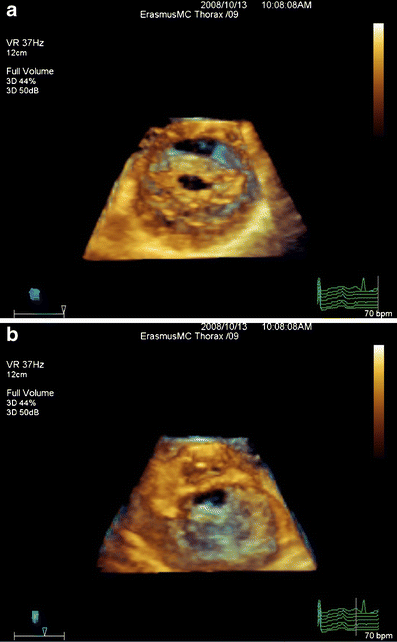

New Scores For The Assessment Of Mitral Stenosis Using Real-Time Three

New Scores for the Assessment of Mitral Stenosis Using Real-Time Three link.springer.com

dimensional echocardiography assessment fig three stenosis mitral